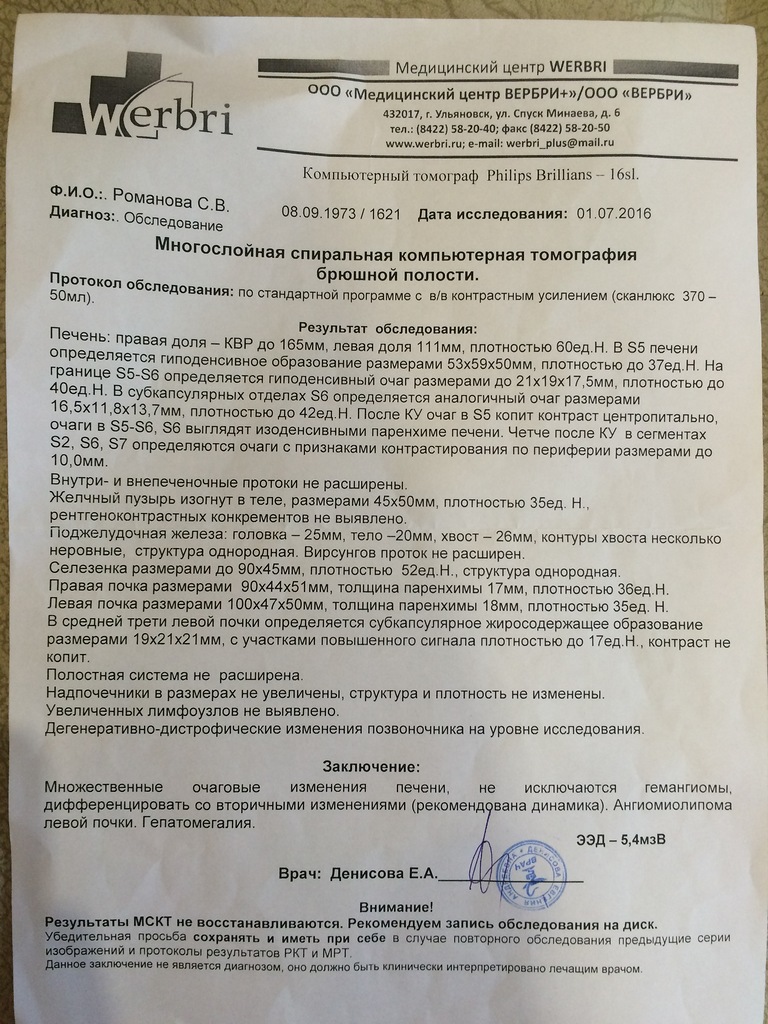

МРТ головного мозга: Расшифровка снимков и Интерпретация

Раздел: Визуальные уроки